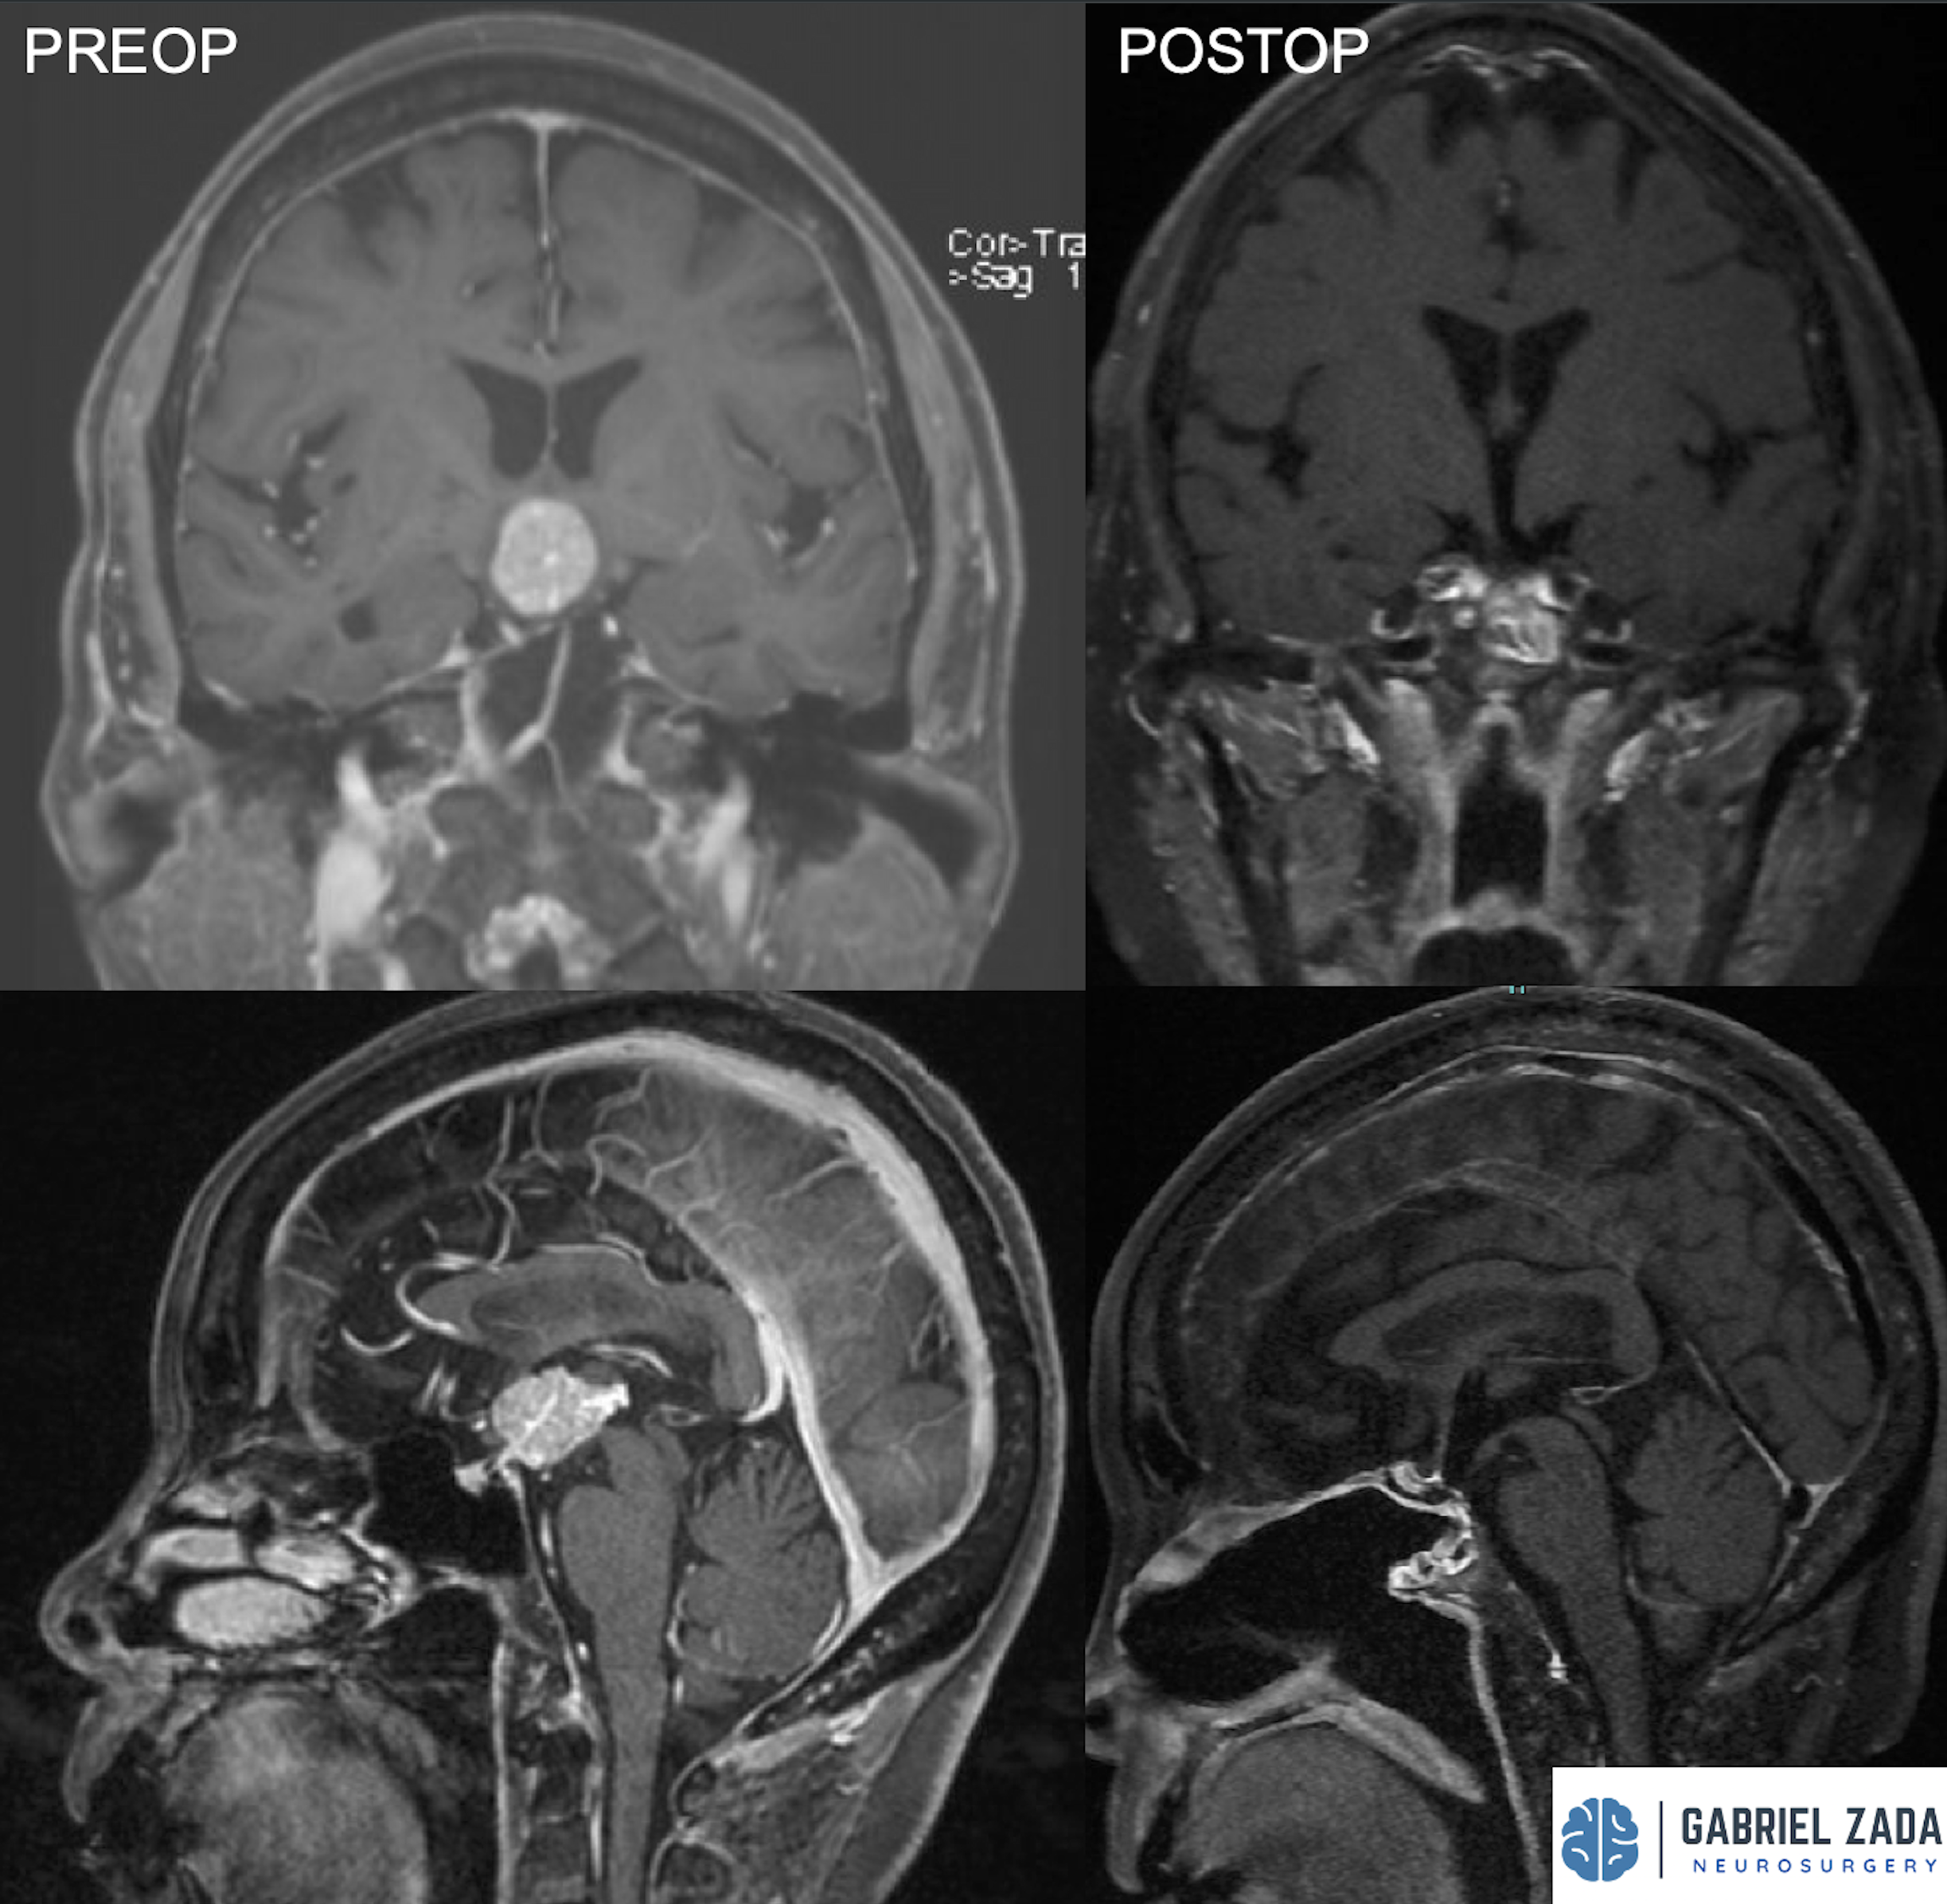

Explore this comprehensive gallery featuring pre‑ and post‑operative imaging of patients with skull‑base tumors treated by Gabriel Zada, MD, MS, FAANS, FACS. These cases highlight Dr. Zada’s expertise in advanced neurosurgical techniques and outcomes.

*Representative cases shown for educational purposes. All images de-identified. Individual results vary.